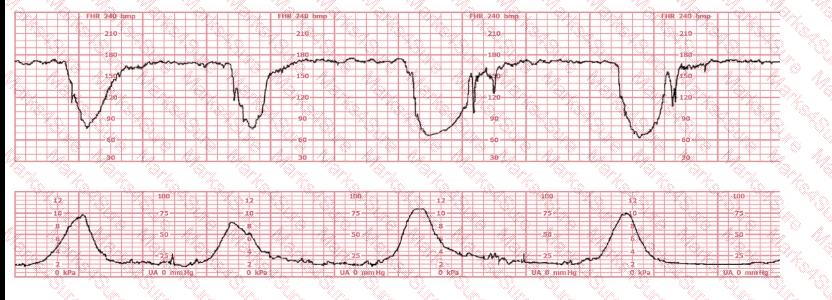

A woman at 38-weeks gestation is admitted to labor and delivery following a fall down the stairs three hours ago. She started feeling contractions in the ambulance. The fetal heart rate tracing shown is on initial evaluation and represents 25 minutes. This tracing is most consistent with a